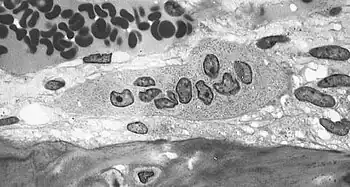

![]() Light micrograph of an osteoclast displaying typical distinguishing characteristics: a large cell with multiple nuclei and a "foamy" cytosol. | |

An osteoclast is a large multinucleated cell and human osteoclasts on bone typically have four nuclei[5] and are 150–200 μm in diameter. When osteoclast-inducing cytokines are used to convert macrophages to osteoclasts, very large cells that may reach 100 μm in diameter occur. These may have dozens of nuclei, and typically express major osteoclast proteins but have significant differences from cells in living bone because of the not-natural substrate.[6][7] The size of the multinucleated assembled osteoclast allows it to focus the ion transport, protein secretory and vesicular transport capabilities of many macrophages on a localized area of bone.

In bone, osteoclasts are found in pits in the bone surface which are called resorption bays, or Howship's lacunae. Osteoclasts are characterized by a cytoplasm with a homogeneous, "foamy" appearance. This appearance is due to a high concentration of vesicles and vacuoles. These vacuoles include lysosomes filled with acid phosphatase. This permits characterization of osteoclasts by their staining for high expression of tartrate resistant acid phosphatase (TRAP) and cathepsin K. Osteoclast rough endoplasmic reticulum is sparse, and the Golgi complex is extensive.[8][9][10]